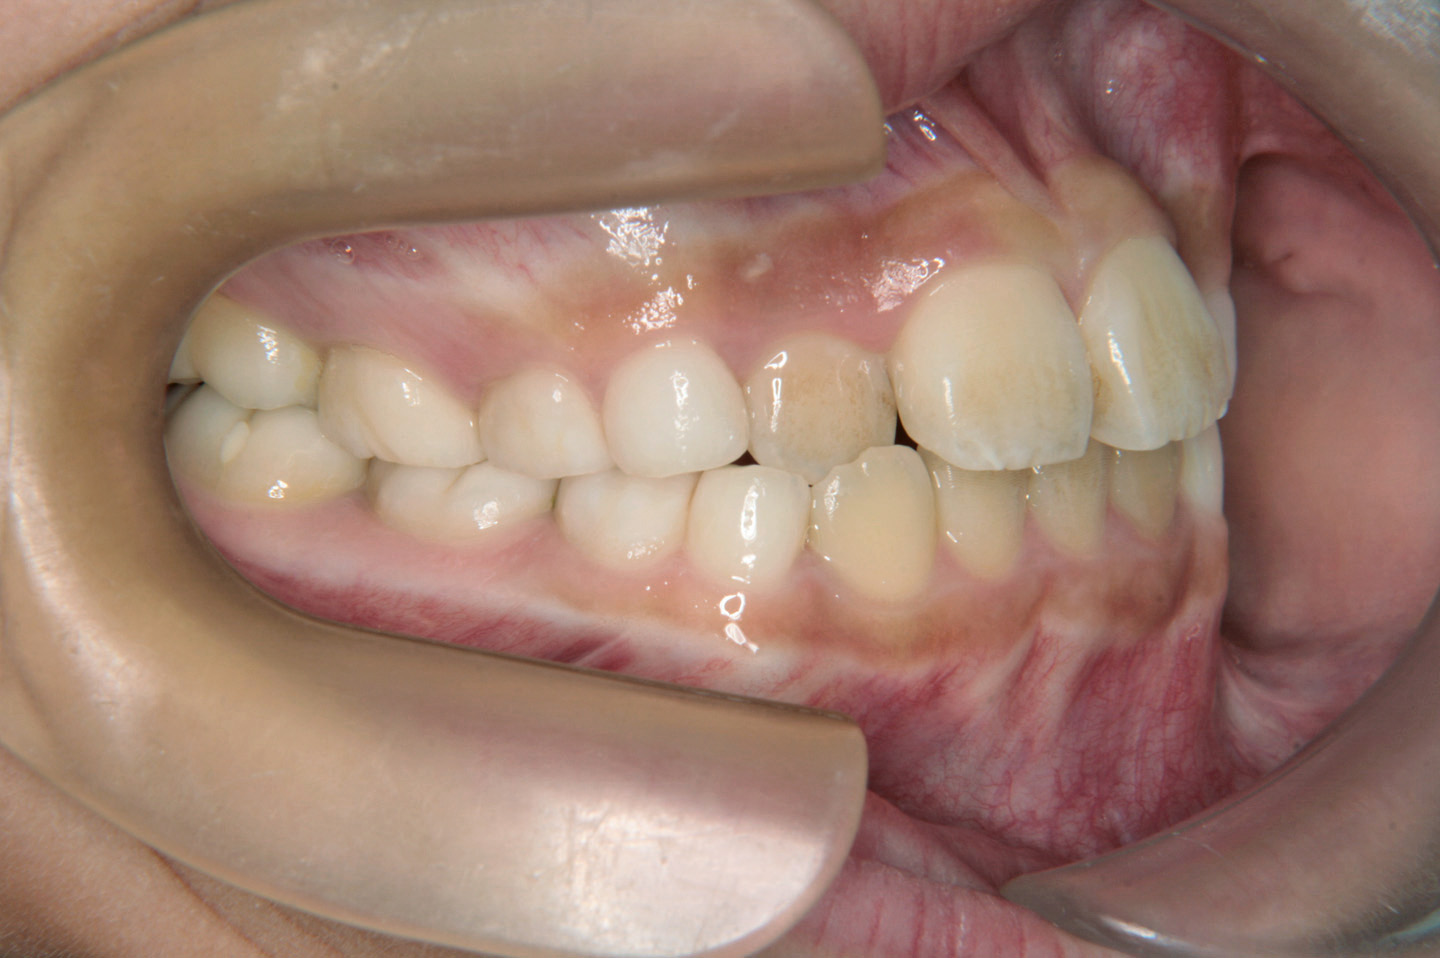

上の前から2番目の歯が内側から生えてきたことを気にされて来院されました9歳の女子です。前期治療としてリンガルアーチを用いて前歯の早期接触を改善し、その後、非抜歯での配列を目標としヘッドギアーで上顎大臼歯の後方への拡大を行いました。エッジワイズ装置(デーモンシステム)で後期治療を行っておりますが、非抜歯で、良好な結果を得ることができました。